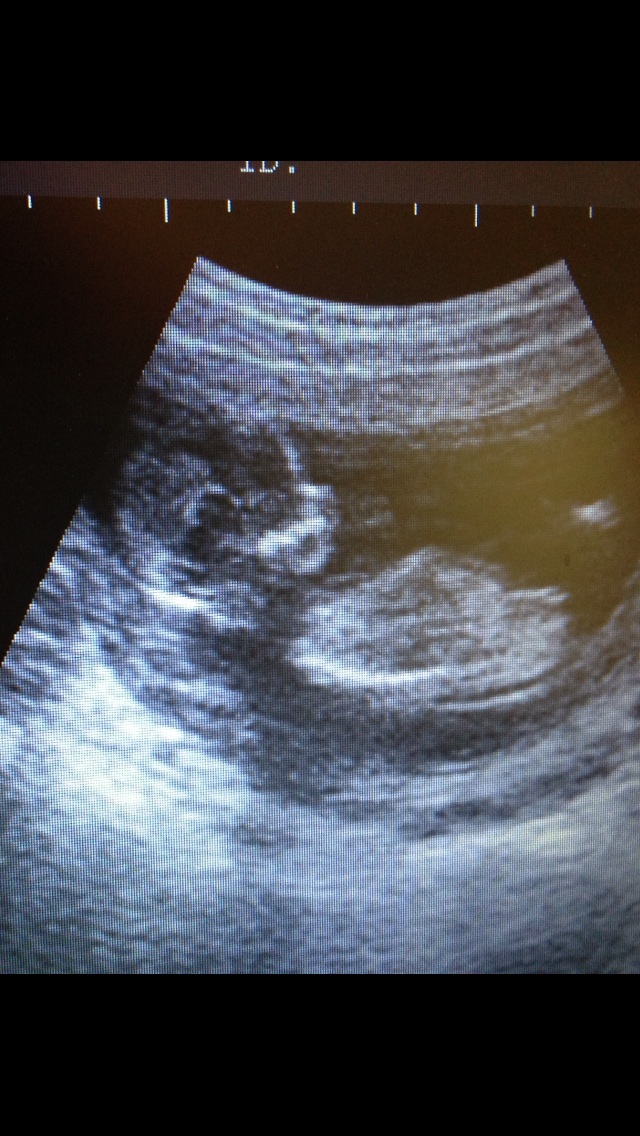

Potty shotAttachment 13625

i think girl x nub is straight in line with spine and potty view has those triangle lines famiilar to girl, head is very roundish too x

I am also thinking girl!

Yep, I think girl too x

Girl

Girl! Congrats :)

Pinky!!